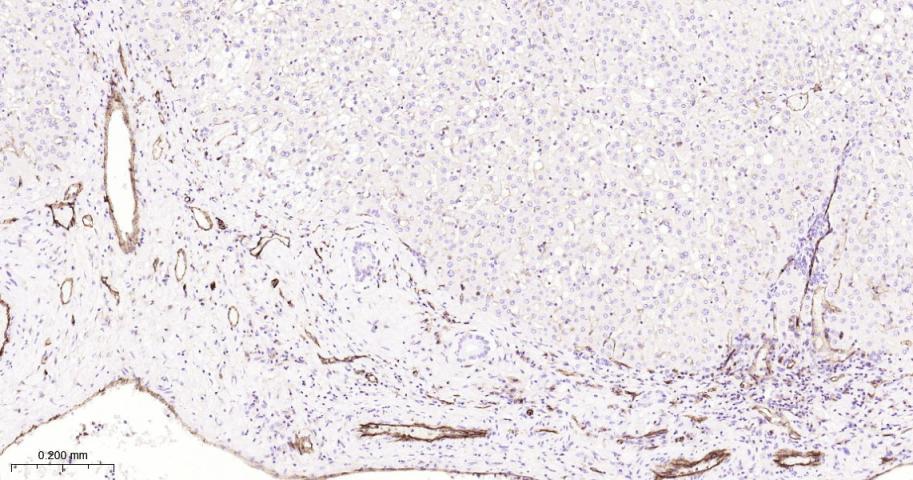

Paraformaldehyde-fixed, paraffin embedded Human Duodenum; Antigen retrieval by boiling in sodium citrate buffer (pH6.0) for 15 min; Antibody incubation with CD31 Monoclonal Antibody, Unconjugated(bsm-10825R) at 1:500 overnight at 4°C, followed by conjugation to the bs-0295G-HRP and DAB (C-0010) staining.

Paraformaldehyde-fixed, paraffin embedded Human Kidney; Antigen retrieval by boiling in sodium citrate buffer (pH6.0) for 15 min; Antibody incubation with CD31 Monoclonal Antibody, Unconjugated(bsm-10825R) at 1:500 overnight at 4°C, followed by conjugation to the bs-0295G-HRP and DAB (C-0010) staining.

Paraformaldehyde-fixed, paraffin embedded Human Spleen; Antigen retrieval by boiling in sodium citrate buffer (pH6.0) for 15 min; Antibody incubation with CD31 Monoclonal Antibody, Unconjugated(bsm-10825R) at 1:500 overnight at 4°C, followed by conjugation to the bs-0295G-HRP and DAB (C-0010) staining.

Paraformaldehyde-fixed, paraffin embedded Human Liver; Antigen retrieval by boiling in sodium citrate buffer (pH6.0) for 15 min; Antibody incubation with CD31 Monoclonal Antibody, Unconjugated(bsm-10825R) at 1:500 overnight at 4°C, followed by conjugation to the bs-0295G-HRP and DAB (C-0010) staining.

Paraformaldehyde-fixed, paraffin embedded Human Colon Cancer; Antigen retrieval by boiling in sodium citrate buffer (pH6.0) for 15 min; Antibody incubation with CD31 Monoclonal Antibody, Unconjugated(bsm-10825R) at 1:500 overnight at 4°C, followed by conjugation to the bs-0295G-HRP and DAB (C-0010) staining.

Paraformaldehyde-fixed, paraffin embedded Human Tonsil; Antigen retrieval by boiling in sodium citrate buffer (pH6.0) for 15 min; Antibody incubation with CD31 Monoclonal Antibody, Unconjugated(bsm-10825R) at 1:500 overnight at 4°C, followed by conjugation to the bs-0295G-HRP and DAB (C-0010) staining.

Paraformaldehyde-fixed, paraffin embedded Human Liver Cancer; Antigen retrieval by boiling in sodium citrate buffer (pH6.0) for 15 min; Antibody incubation with CD31 Monoclonal Antibody, Unconjugated(bsm-10825R) at 1:500 overnight at 4°C, followed by conjugation to the bs-0295G-HRP and DAB (C-0010) staining.

Paraformaldehyde-fixed, paraffin embedded Human Lung Cancer; Antigen retrieval by boiling in sodium citrate buffer (pH6.0) for 15 min; Antibody incubation with CD31 Monoclonal Antibody, Unconjugated(bsm-10825R) at 1:500 overnight at 4°C, followed by conjugation to the bs-0295G-HRP and DAB (C-0010) staining.